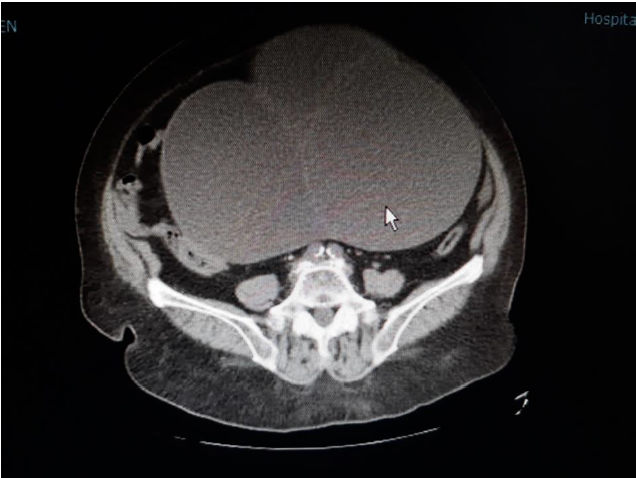

Se solicita de urgencia preoperatorio con hallazgo de leucocitosis leve sin neutrofilia y estudio de coagulación normal. En la TC de abdomen sin contraste iv (fig. 3) solicitada se aprecia una gran masa abdominopélvica que mide 26*19*16 cm (axial, longitudinal y anteroposterior), predominantemente quística, con septos en su interior, su polo inferior se encuentra orientado hacia hemipelvis derecha donde no es posible descartar dada la ausencia de contraste de la prueba que pueda tener un componente sólido. Ambos anejos se encuentran desplazados hacia la derecha e impresionan estar en contacto entre ellos sugiriendo torsión anexial. Hematometra. Mínima cantidad de líquido libre en la gotiera paracólica izquierda. No se objetivan otros hallazgos de interés.